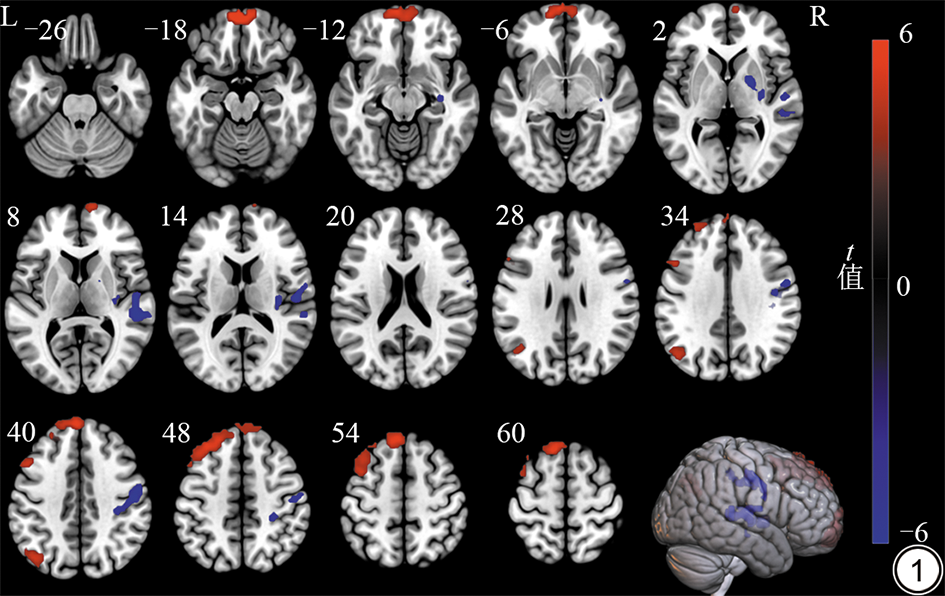

PD与HC两组受试者全脑DC差异有统计学意义的脑区有6个团块(团块1~6,团块水平FWE校正,P<0.001),其中团块1~3表现为PD患者低于HC组,团块4~6则表现为PD患者高于HC组。基于MNI自动解剖标记(automatic anatomical labeling, AAL)模板,团块1峰值点坐标位于右侧豆状核苍白球;团块2峰值点坐标位于右侧颞上回,余主要位于右侧中央沟盖;团块3峰值点坐标位于右侧中央前回,余主要位于右侧中央后回;团块4峰值点坐标位于左侧直回,余主要位于左侧眶部额上回和两侧眶部额中回;团块5峰值点坐标位于左侧角回;团块6峰值点坐标左侧内侧额上回,余主要位于左侧额中回和左侧背外侧额上回。具体内容见表2图1

图1  PD患者与HC组受试者全脑DC差异脑区示意图。蓝色代表PD组低于HC 组,红色代表PD组高于HC组。PD:帕金森病;HC:健康对照;DC:度中心性。

Fig. 1  Whole-brain map of DC differences between PD patients and HC subjects. Blue indicates the PD group is lower than the HC group, while red indicates the PD group is higher than the HC group. PD: Parkinson's disease; HC: healthy control; DC: degree centrality.